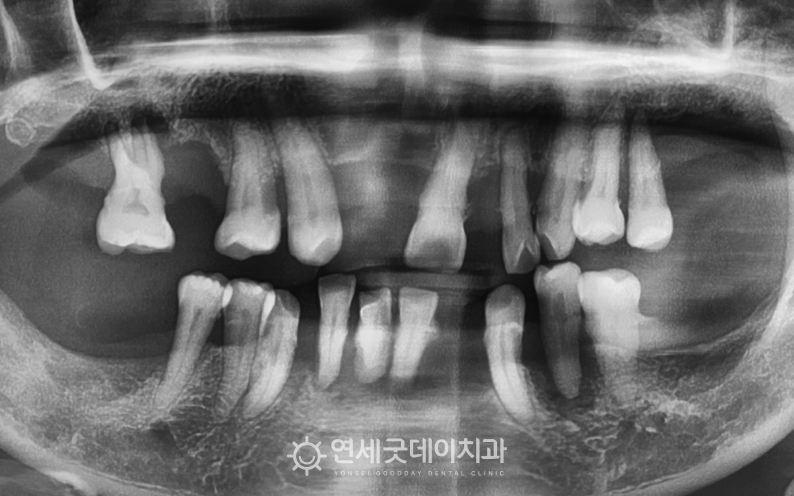

▲ 치료 전 X-ray (촬영시기 : 2023년 3월)

앞니를 포함하여 듬성듬성 치아가 빠진 상태였으며

전체적으로 골소실이 많이 진행된 모습이 관찰되었습니다.